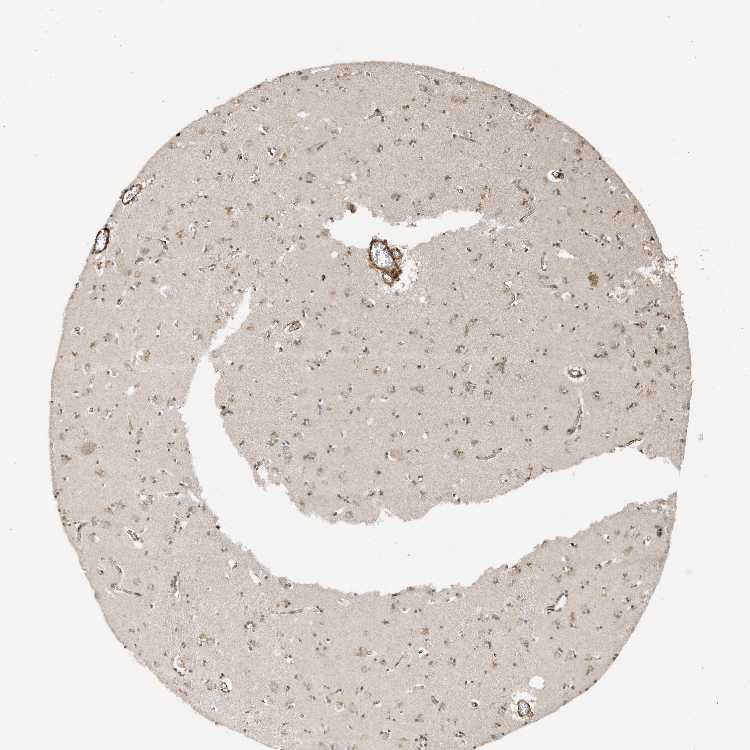

CAUDATE - Antibody stainingi

Antibody staining in the annotated cell types in the current human tissue is reported as not detected, low, medium, or high, based on conventional immunohistochemistry profiling in selected tissues. This score is based on the combination of the staining intensity and fraction of stained cells.

Each image is clickable and will lead to virtual microscopy that enables deeper exploration of all samples and also displays staining intensity scores, fraction scores and subcellular localization as well as patient and tissue information for each sample.

Antibody CAB034070

Glial cells Low

Neuronal cells Medium